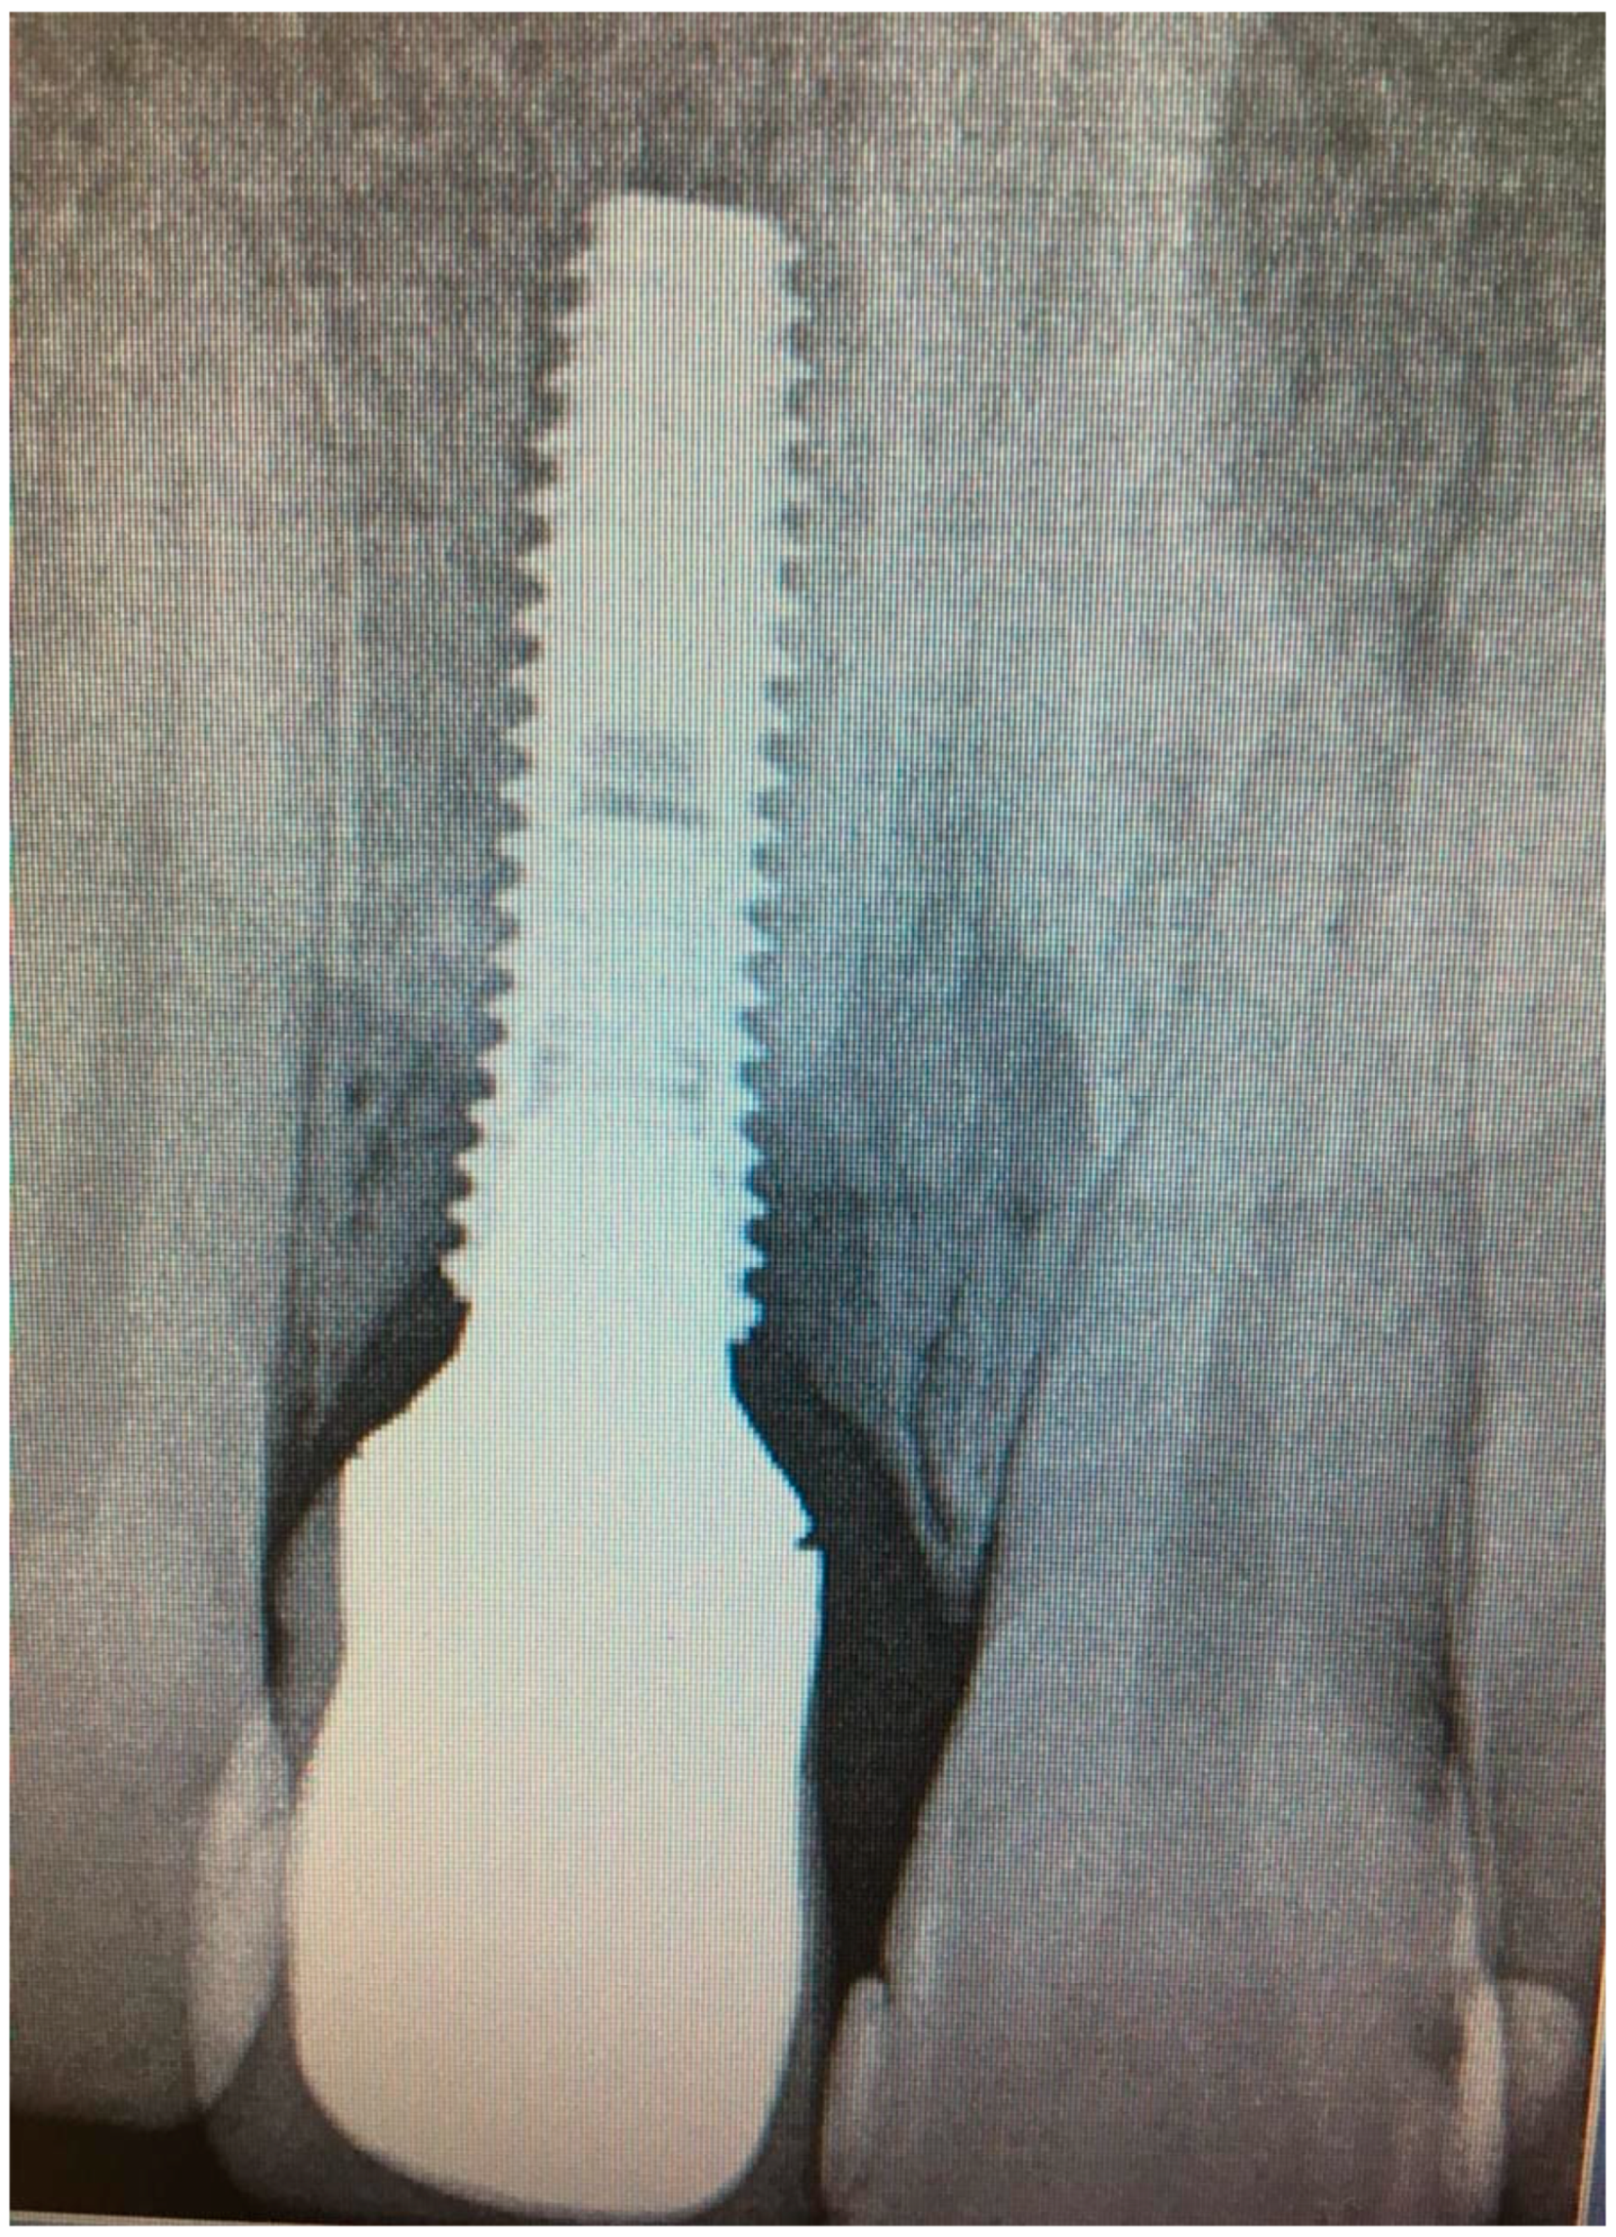

2.1. Case Report 1

2.2. Case Report 2

2.3. Case Report 3